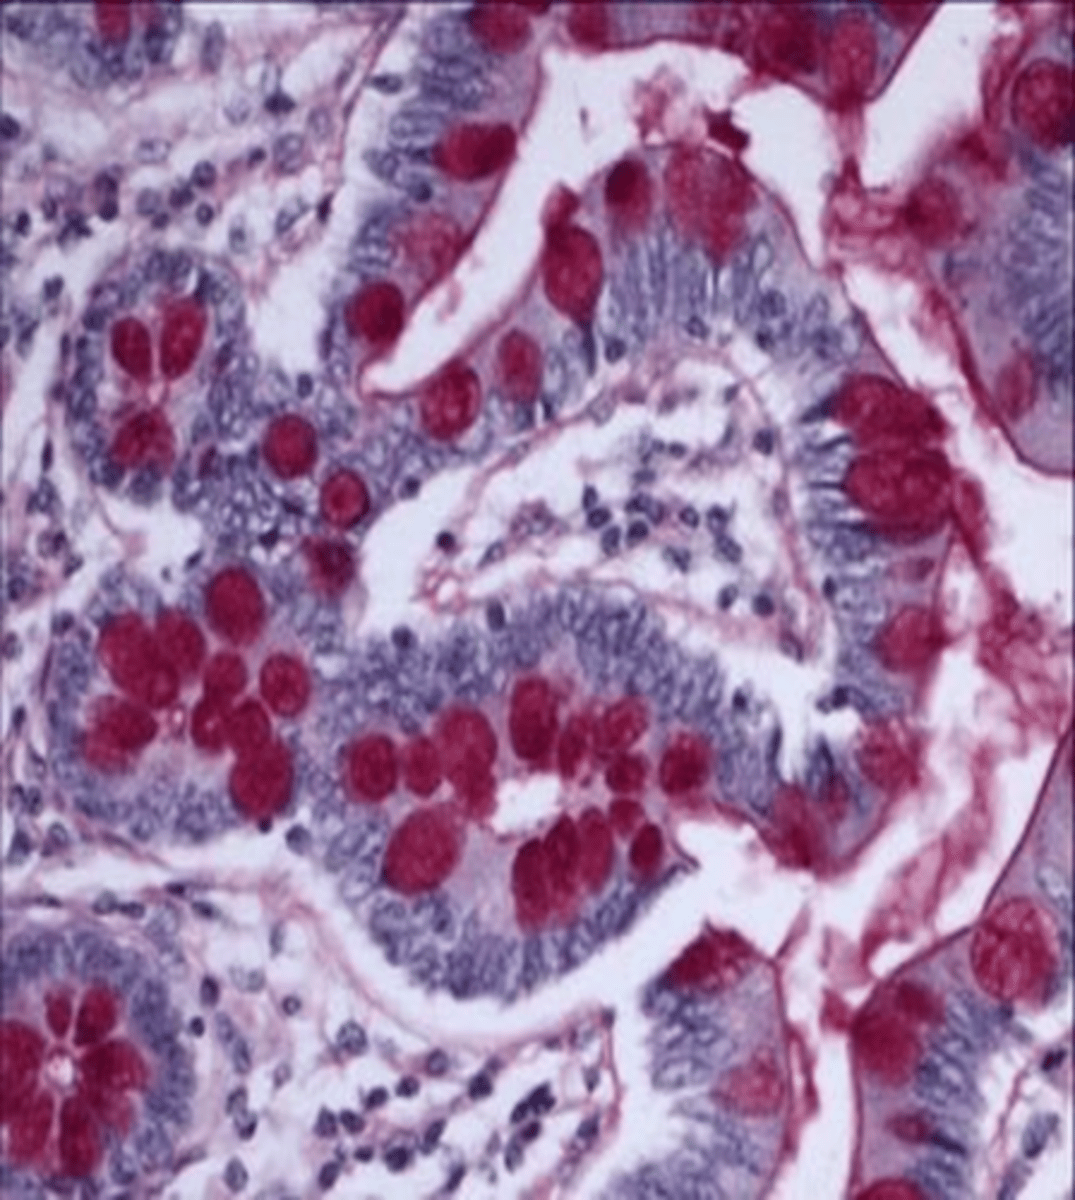

What does Periodic Acid-Schiff stain?

polysaccharides; glycogen storage disease or fungal hyphae/yeast